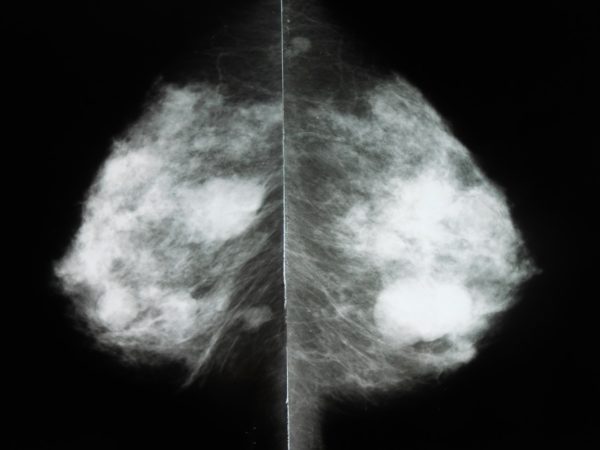

Определить форму заболевания можно с помощью ультразвукового исследования и маммографии, которые помогают визуализировать опухоль и оценить её характеристики. Важно помнить, что при обнаружении уплотнений в груди необходимо обратиться к врачу для диагностики и, при необходимости, биопсии. Многие женщины отмечают, что своевременное обращение к специалисту и регулярные обследования помогают избежать осложнений и сохранить здоровье.

Что касается наличия кальцинатов в грудной железе, определить их можно только с помощью рентгена или маммографии.